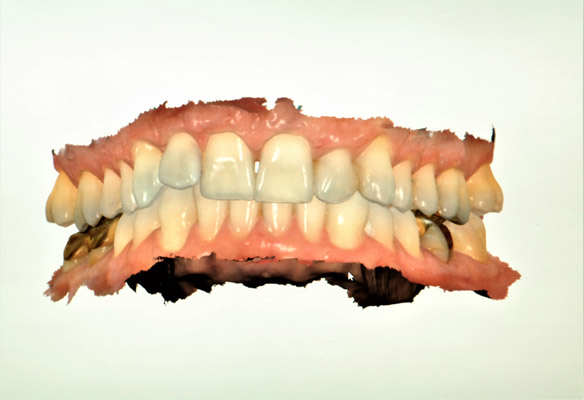

DIGITAL INTRAORAL SCANNER

Scanner can capture the true representation of your dentition in a digital format as opposed to the conventional manual impression technique. This digitally captured image can be used in variety of way. The images can be used to fabricate crowns, bridges, partial dentures, bruxing appliances and more. Using digital workflow allows for an additional tool to improving patient care.